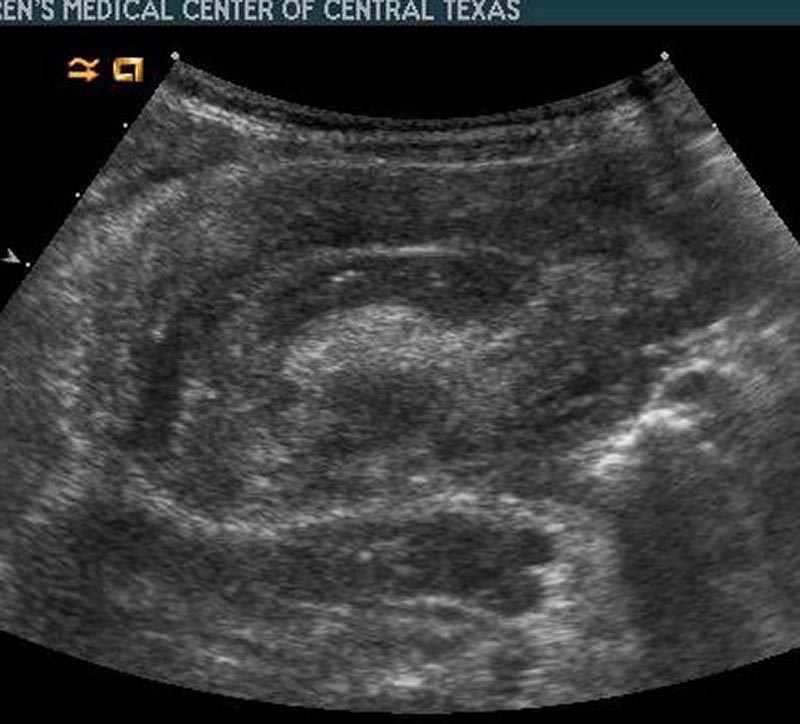

10-month-old male infant presents to the ED by EMS with vomiting and altered mental status (AMS). Infant arrives to the ED awake but poorly interactive. Ultimately, the infant will be diagnosed with intussusception and hypovolemic shock based on the history, physical exam and ultrasound findings. Learners are expected to establish a differential diagnosis of AMS appropriate for an infant, demonstrate appropriate resuscitative interventions, and use appropriate imaging and labs to help identify the cause of AMS.